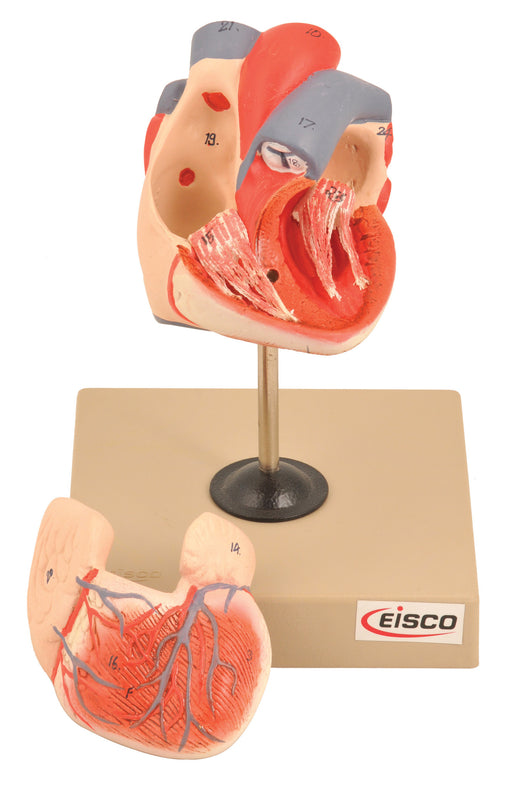

Eisco Labs Life Size Human Heart Model on Base; 2 Parts

Detailed anatomy Vividly hand painted Detailed Internal Anatomy (atria, ventricles, and valves) can be studied due to removable piece Identificati...

View full detailsAM798081AS -

Giant Human Heart Model

3 times life size 7 parts 9" x 8" base Includes a Key card calling out 23 structures Includes: (1) Giant Human Heart Model Get...

View full detailsAM75AS -

Eisco Labs Model of Human Heart Conditions Pathology; Larger than life size (10"); Artery Cross sections 2.5" in diameter

Heart on stand - larger than life size (approx. 10") Four artery cross sections (2.5" in diameter) showing the progression of atherosclerosis Vivi...

View full detailsAM0280 -